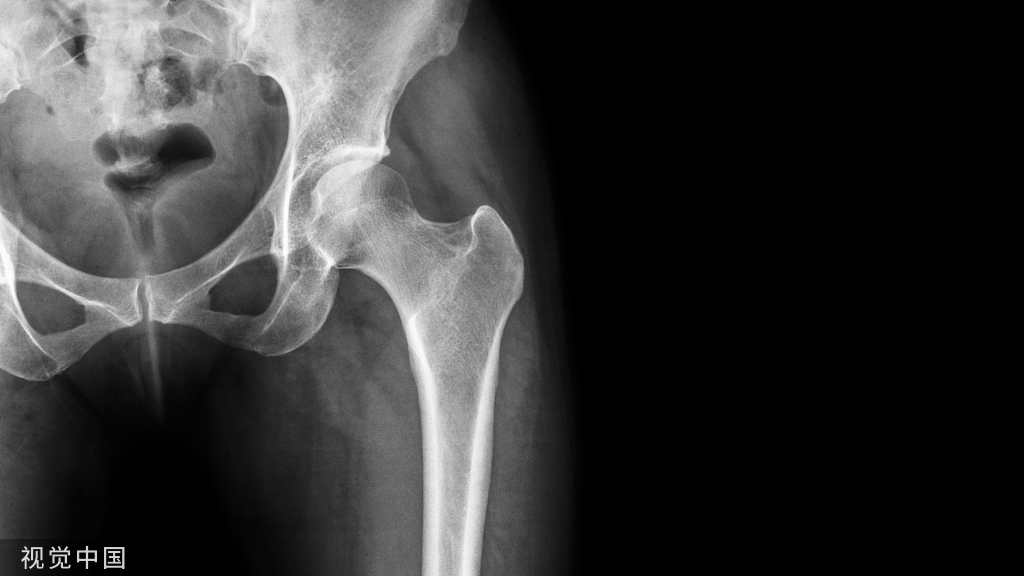

使用多孔钽假体(左髋关节)重建Paprosky IIB缺损的X线片:a)术前和b)术后10年的正位X线片。

应用多孔钽假体重建Paprosky 3A缺损术的一例(左侧髋关节)的X线片:术前(左)、术后(中)和10年后(右)的正位X线片